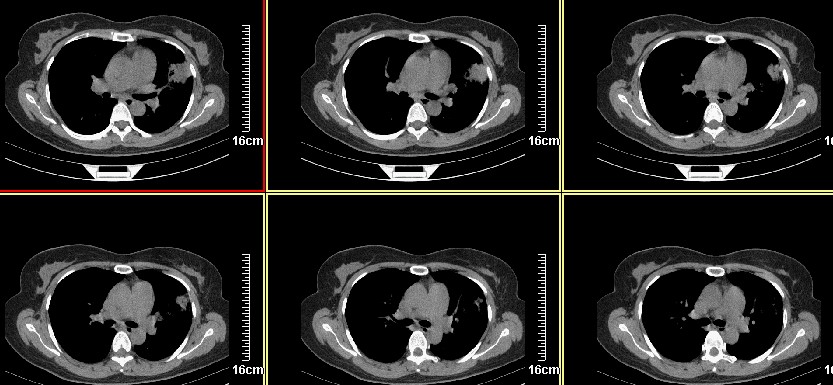

标题: CT8227:左肺上叶占位???? 又有新进展 一周之后 复查 [打印本页]

标题: CT8227:左肺上叶占位???? 又有新进展 一周之后 复查

一周之后 复查结果 5mm扫描 40多岁 我们医院的护士

病史?1.首先考虑左肺上叶占位(ca可能);

2.继发型肺tb?

3.单纯感染不除外。

左上肺周围型肺癌可能性大,楼主片子太小

考虑左肺上叶周围型肺癌可能性大.

左肺上叶肿块,肺窗周围有“晕征”,纵隔窗有毛刺,临床资料???只能考虑占位???